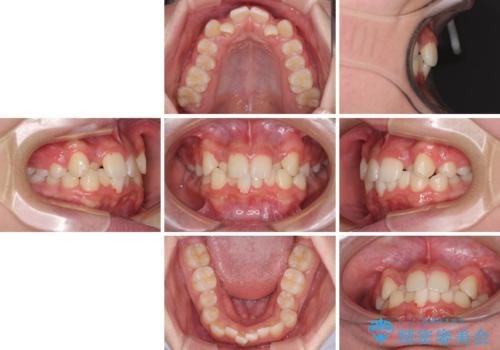

中学生のワイヤー矯正 クロスバイトを短期間で改善

- 前歯のクロスバイトを気にして来院された患者様です。

中学生であることから、治療期間を短縮できると判断し、ワイヤー矯正にて短期間で治療を行うこととしました。

叢生のため磨き残しの多い歯列でしたが、1年弱で治療を終了でき、磨き残しや歯肉の腫れが著しく改善されました。